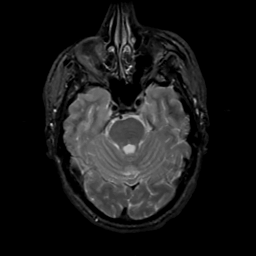

MR Study #8, March 31, 1991 -- Slice #15

[Home][Help][Clinical][Tour 1][Tour 2] Slice 15